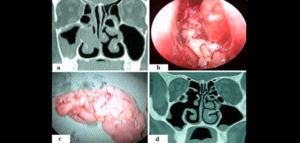

El Papiloma invertido de la cavidad nasal y senos paranasales es un tumor epitelial benigno de etiología desconocida siendo un subtipo del papiloma de Schneider.